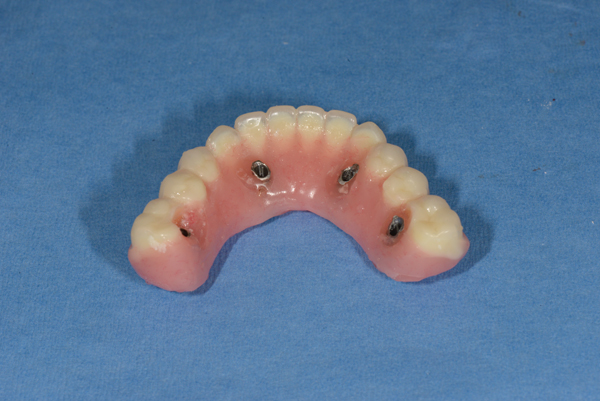

Fig 16. Indirect denture conversion—The indexed provisional prosthesis is modified for passive attachment of the posterior titanium cylinders to the prosthesis using heat-cured acrylic under pressure. This process is repeated for the anterior indexed implants, leading to a higher quality provisional with increased strength.

Figure 16

The dental technician fabricates a master cast with a soft-tissue model while the indexing and VDO procedures are performed. A silicone material is added around the implant analogues in the surgical impression before model pouring with zero expansion stone (Figure 14 and Figure 15). The soft-tissue model is removed to verify a precise fit of the temporary titanium cylinders indexed in the mouth to the master cast. The indexed provisional prosthesis is modified to allow passive attachment of the posterior temporary cylinders to the prosthesis using heat-cured acrylic processed under pressure. The technician then removes the cold-cure acrylic that was used to index the two anterior temporary components and re-secures them with fresh heat-cured acrylic under pressure (Figure 16). The intaglio surface of the provisional prosthesis is finished with cold-cure acrylic on the master cast and polished to ensure a convex surface with sufficient space to allow for tissue swelling and access for hygiene.

By following the described protocol, insertion and delivery of the provisional prosthesis should proceed without any difficulty. Retaining screws are secured at 15 Ncm. Access holes are filled with Teflon tape and temporary filling material. Functional occlusal adjustments are performed intraorally to achieve light bicuspid and anterior contacts. Esthetic and phonetic parameters are evaluated after full recovery of the anesthesia. Follow-up visits to monitor healing and occlusion are scheduled at 1 and 3 weeks post procedure. The prosthesis is not removed for 8 weeks, at which time an implant assessment is performed to evaluate implant integration and peri-implant health. The authors believe that any complications are better addressed at this stage of the treatment.

The definitive prosthesis is delivered between 6 and 12 months later, allowing time for tissue remodeling. Typically, the preferred definitive restoration is a highly esthetic acrylic hybrid prosthesis secured over a CAD/CAM–milled titanium bar designed for a full acrylic wrap on the intaglio surface of the restoration with pink restorative material that simulates gingiva. This type of restoration is cost-effective and easily repaired or modified. Alternative options include fixed zirconium bridges, fixed zirconium framework with individual cemented crowns, and porcelain-fused-to-metal restorations. Regular recall every 3 to 4 months is paramount for maintenance and to identify and rapidly treat potential biologic or biomechanical complications.